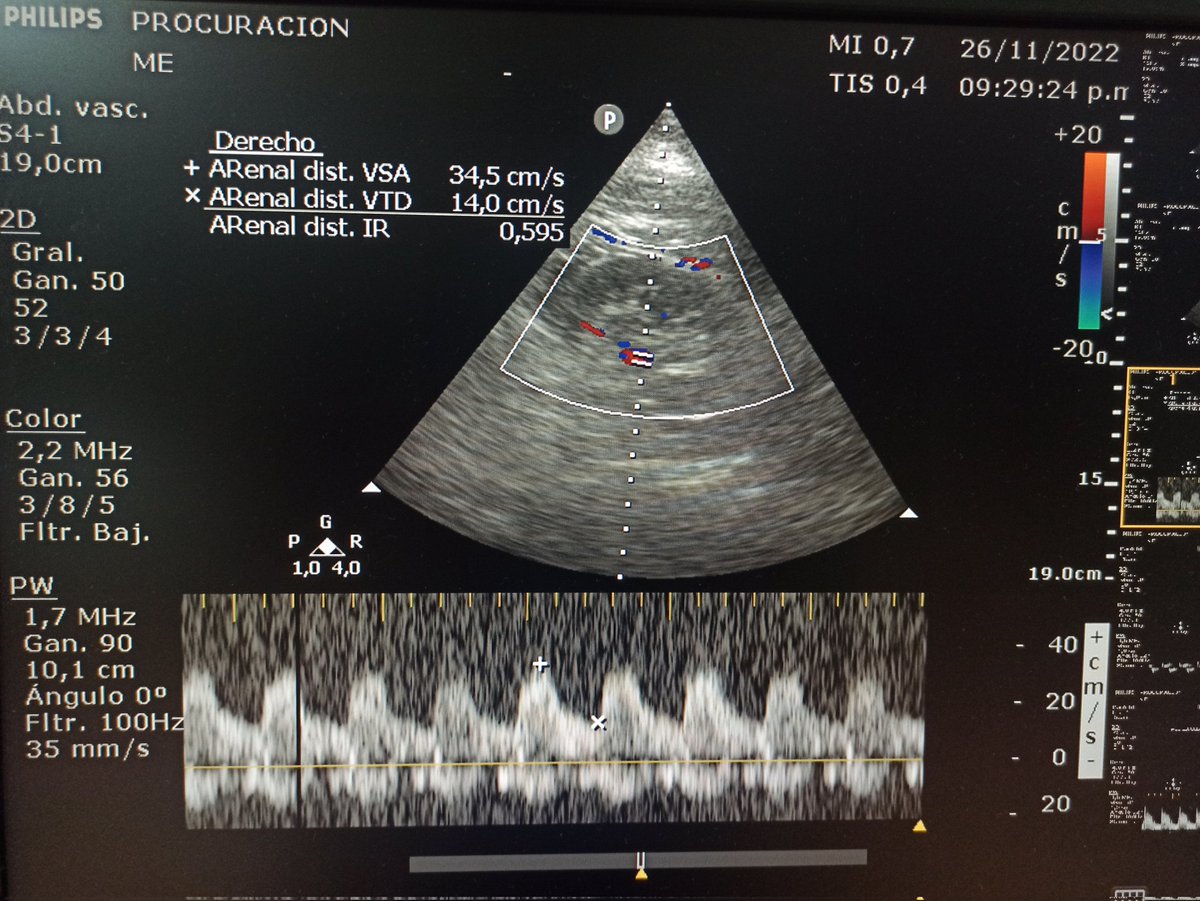

Dx Meningitis Bacteriana + HSA GCS 3/15 midriasis arreactiva, sin reflejos de tronco, test de apnea abortado por bradicardia. EEG no disponible Hilo completo desde... twitter.com/matibriz/statu… @Issac80 @ABCDEcografia @JuanFolco @ASARUC1